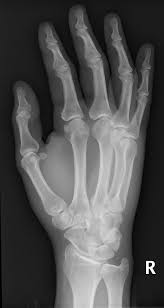

Two spiral fractures sustained following only minor trauma. Complete fractures are categorized based on the way the bone breaks. It occurs due to a rotational, or twisting, force. Try our newest study sets that focus on spiral fracture to increase your studying efficiency and retention. Detailed step by step desription of intramedullary nailing for simple fracture, spiral located in our module intramedullary fixation is valuable and appropriate for the majority of tibial fractures. Other articles where spiral fracture is discussed: A spiral fracture is a bone fracture occurring when torque is applied along the axis of a bone.1 spiral fractures often occur when the body is in motion while one extremity is planted. Spiral fracture femur (there is a significantly displaced spiral fracture of the proximal femoral. A spiral fracture, also known as torsion fracture, is a type of complete fracture. A spiral fracture is a bone fracture caused by a twisting force. A spiral fracture is usually treated right away with surgery. Summary summary (text) medline pmcid list. Know ways to lower your risks in the first place.

Spiral fracture — beware the horns 03:03. A spiral fracture is a bone fracture caused by a twisting force. A fracture, sometimes called a torsion fracture, in which a bone has been twisted apart. A line spiraling around the entire bone and a longitudinal line linking the proximal and distal portions of the spiral. A spiral fracture, characterized by a helical break, commonly results from a twisting injury.